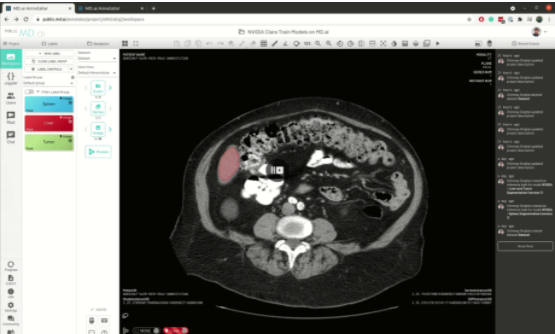

使用 NVIDIA Clara 构建的医疗成像 AI 模型现在可以在云计算的 MD.ai 上本地运行,从而使用现代 web 浏览器实现协作模型验证和快速注释项目。这些 NVIDIA Clara 模型可免费用于任何 MD.ai 合作研究项目,如器官或肿瘤分割。

MD.ai 提供了一个基于 web 的云本地注释平台,支持临床医生和研究人员团队之间通过共享工作空间进行实时协作。您还可以加载多个深度学习模型以进行实时评估。

该平台为数据集构建和 AI 项目创建提供了一个简单无缝的界面。它为用户提供了一套广泛的工具,用于注释数据和构建机器学习算法,以加速人工智能在医学中的应用,特别关注医学成像。

图 3 。显示大脑分割的 MD.ai 用户界面 。

将此功能与在 MD.ai 平台上快速部署 Clara 训练模型 MMAR 的能力相结合,可以为您提供一个端到端的工作流,该工作流涵盖快速模型开发、模型训练、微调、推理以及快速评估和可视化。这种端到端的能力简化了模型从研发到生产的过程。